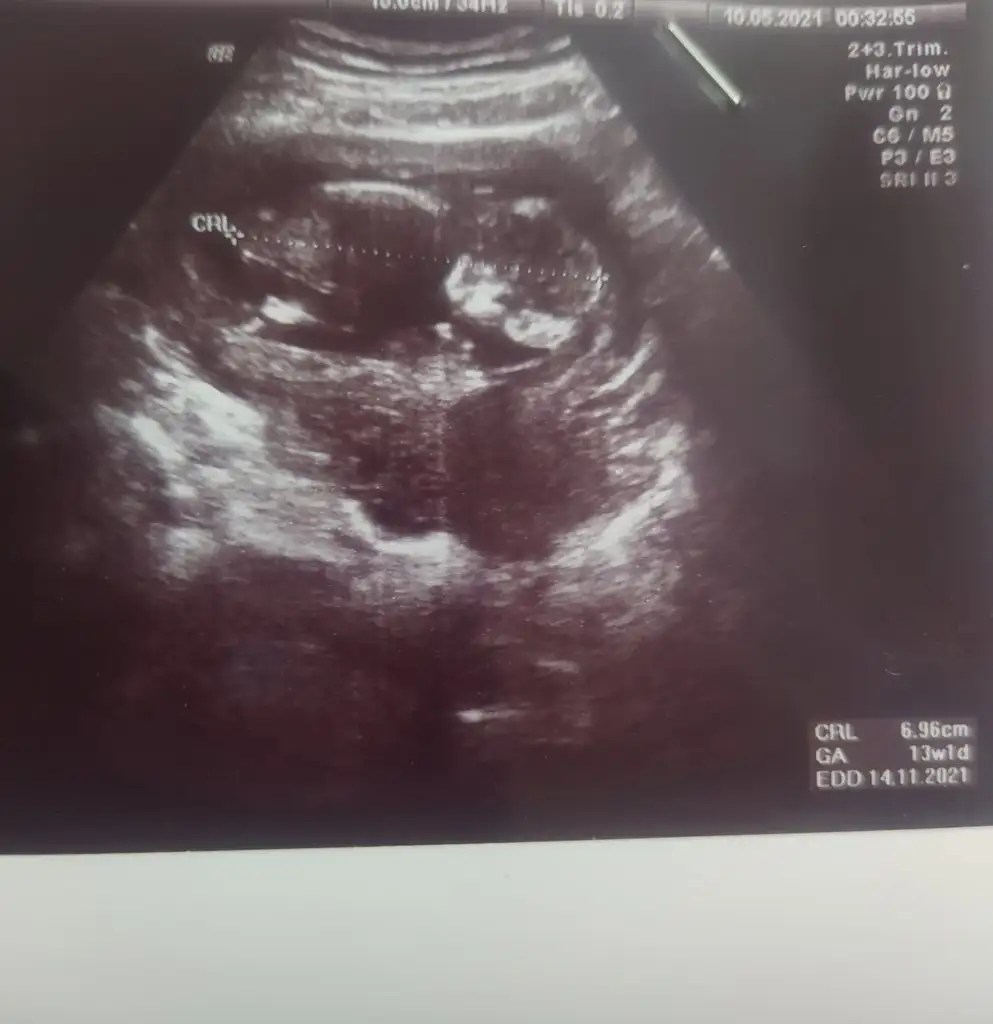

Ikra hanım merhaba 11+1den karından usg atıyorum rica etsem tahminde bulunur musunuz arkadaşım için bana kız demiştiniz doğru cıktı 🤭😊

Anketimi oylarsaniz sevinirim sağlıkla gelsin prenses 🥰